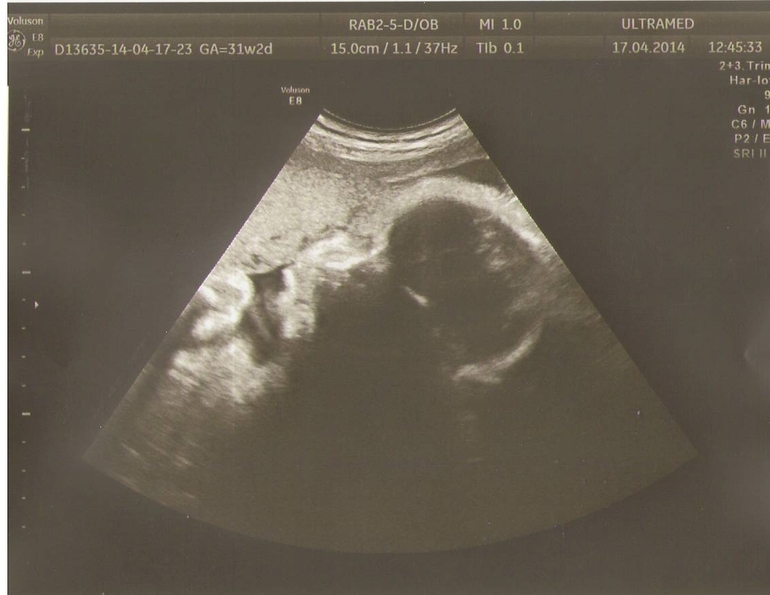

ЧТ(сегодня): Поехали на УЗИ. Матюшка наш вешает 1745 гр, на 100 гр как всегда больше Дани на этом сроке. Бедро 59 мм, плечо 53 мм, голова 293 мм, животик 269 мм. Срок 31-32 недели.Сказали родимся с 14-17 июня. Показали нам достоиноство наше во всей красе, точно не ошиблись что мальчик))))Выкатил блин)))) Смотрят размеры мозга, а на голове волосы, узистка аж прифигела, капец длинные!!!!!!!!!!!!!!!!!!!И как у меня нет изжоги!!!!!!!!!!!!!! Врач как всегда сделала нам и 2Д и 3Д. Правда ракурс вообще неудачный, лежит лицом уткнулся в плаценту. Я всю дорогу ехала и обижалась, 2Д фото можно было и поудачней сделать(((((((( Носик вроде небольшой у нас, а вот губешки пухленькие-припухленькие.Обвитий нет, патологий органов тоже,ТТТ. Почки мои подвели,правда продержались в 2 раза дольше чем в первую Б: каликоэктазия(((((

Вот и фото нашего младшенького